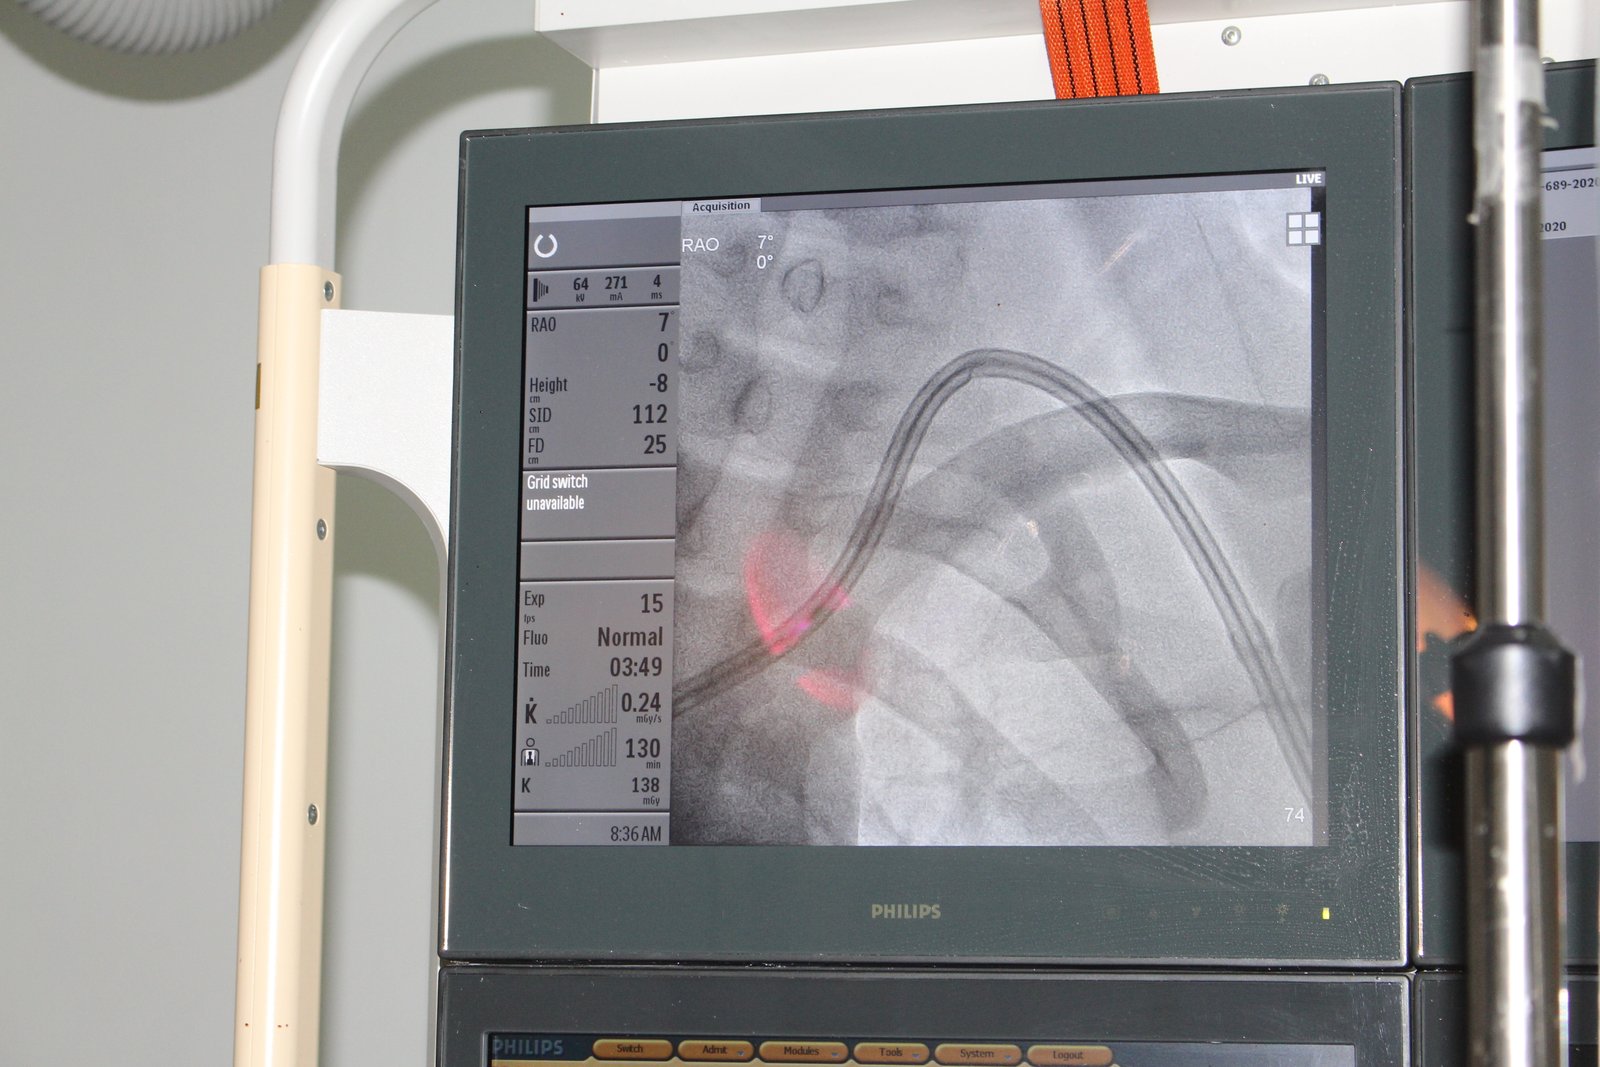

بلغ عدد عمليات القسطرة الكلوية التي تجريها مؤسسة الشفقة لرعاية مرضى الفشل الكلوي ومرضى السرطان لمرضى الفشل الكلوي خلال العشرين يوما منذ بداية تنفيذ المشروع 25 عملية.

وأوضح الأستاذ واثق القرشي رئيس المؤسسة ، إن مشروع عمليات القسطرة الكلوية ، يسهم في إنقاذ حياة العشرات من مرضى الفشل الكلوي ، الذين هم بحاجة ماسة لإجراء مثل هذه العمليات ، للتخفيف من معاناتهم وآلامهم المستمرة.

وقال القرشي في تصريح صحفي ، إن هناك العشرات بل المئات من المرضى ، موجودون في مختلف محافظات الجمهورية ، ويحتاجون إلى مثل هذه العمليات ، لإجراء جلسات الغسيل الكلوي أو الغسيل الدموي اللازمة لتجنيبهم أية مضاعفات مرضية خطيرة ، وإنقاذهم من الموت المحقق ، في حالة عدم إجراء عمليات الغسيل الكلوي.

من جهته قال الأستاذ منصور القطريفي المدير التنفيذي للمؤسسة ، إن مشروع إجراء عمليات القسطرة الكلوية ، يتم تنفيذه بالتعاون مع مستشفى جامعة العلوم والتكنولوجيا صنعاء ، حيث تتم هذه العمليات بجهود عدد من ٲطباء المستشفى وفي مقدمتهم الدكتور شفيق العماد استشاري أمراض الكلى ، والدكتورة إلهام الظليمي إخصائية أمراض الكلى.

مؤكدا إن المشروع سيسهم في دعم أكثر من 40 مريضا ومريضة من مختلف محافظات الجمهورية ، وإنه يأتي في إطار الرعاية الصحية التي تقدمها المؤسسة للآلاف من مرضى الفشل الكلوي ، سواء منهم الموجودين في السكن التابع لها أو المرضى الذين يأتون من خارج السكن.